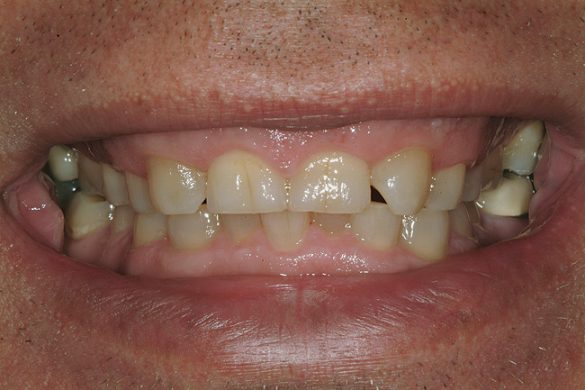

Un bărbat în vârstă de 48 ani, clinic sănătos, s-a prezentat pentru consultaţie, reclamând în principal zâmbetul său dezagreabil. Era îngrijorat cu privire la pierderea progresivă a structurii dentare pe care a constatat-o în decursul ultimilor ani şi cu privire la colorarea generalizată şi afişarea inadecvată a dinţilor şi gingiilor sale. Imaginile retractate preoperatorii relevau o formă de arcadă îngustă cu înghesuire minoră, uzură severă şi eroziune, alături de formarea unor torusuri voluminoase în regiunile maxilare vestibulare1 (fig. 1).

Fiind un consultant de succes de software pentru calculatoare care se întâlneşte săptămânal cu clienţii săi, era totodată conştient de faptul că într-o piaţă competitoare un zâmbet atractiv poate oferi beneficii. Un sondaj efectuat de Academia Americană de Stomatologie Cosmetică (American Academy of Cosmetic Dentistry, AACD) a dezvăluit faptul că o persoană cu un zâmbet agreabil este mult mai atrăgătoare în numeroase privinţe şi poate oferi un avantaj în contextul întâlnirilor de afacerilor.2 Pacientul s-a consultat premergător cu un protetician care i-a recomandat o abordare tradiţională, constând în acoperire totală cu coroane metalo-ceramice pentru a deschide ocluzia şi a îmbunătăţi estetica.

O fotografie iniţială a zâmbetului a evidenţiat afişarea în exces a gingiei, iar măsurătorile au dezvăluit o lungime a incisivilor centrali de 8,5mm (faţă de ideal 11,5mm).7,8

Fotografiile finale ale acestui caz au pus în evidenţă genul de rezultate care se pot obţine urmând sistemele şi tehnicile dovedite (fig. 8-11). S-au realizat obiectivele de îmbunătăţire a raportului “alb-roz” alături de cele legate de zâmbetul pacientului. Perceperea în mod clar a obiectivelor acestui caz şi capacitatea de a comunica cu acurateţe cu pacientul şi ceramistul reprezintă o parte din cheia succesului.